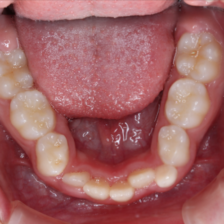

短期間かつ低価格で。

だらだらと長期間治療をするのではなく、ベストなタイミングを見計らい、一気に治療を終わらせます。